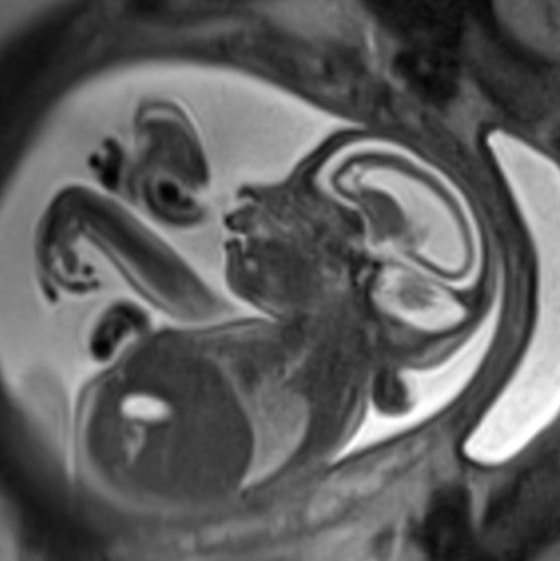

Satu was referred to Children’s National Health System in Washington, which has a magnetic resonance imaging (MRI) machine that can image a developing fetus.

“In the MRI, they really saw clearly all the structures of the brain,” Satu said. “That was helpful. They could show us the picture and it somehow made it very concrete.”

It looked bad, says Dr. Roberta DeBiasi, who helped treat Satu at Children’s.

“As the brain develops, there are different layers that develop while the baby is in the womb,” DeBiasi told NBC News. “These were basically absent. There were some zones that were just completely undetectable.”

That suggested the virus had destroyed the developing tissue, and once damaged in this way, it doesn’t grow back.

“These were not possible or slight findings. They were severe.”

“This particular MRI was so deficient in brain tissue that most people felt this child was extremely unlikely to make it through the pregnancy and unlikely to make it after delivery,” DeBiasi said.

If the fetus survived to be born, there would be profound damage. “The child would never walk or talk and would need constant, 24/7 care through its life, which would be a short one,” Satu said. There was a risk of constant epileptic seizures. “That was a dire prognosis.”